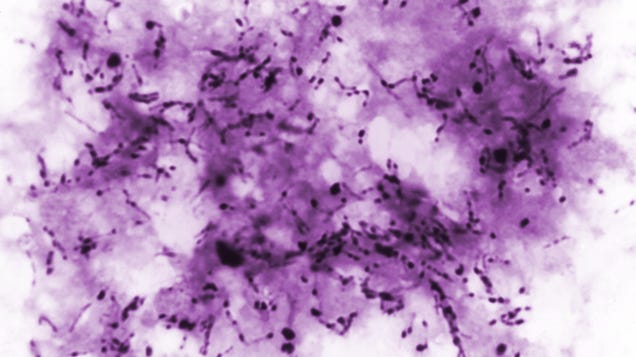

A contaminated batch of donated bone tissue is the likely source behind a strange outbreak of tuberculosis, according to federal health officials at the Centers for Disease Control and Prevention as well as the Food and Drug Administration. As many as 113 people who went in for spinal repair surgery are thought to…

Source: Gizmodo – Bizarre Outbreak of Tuberculosis Linked to Donated Bone Grafts, CDC and FDA Officials Say